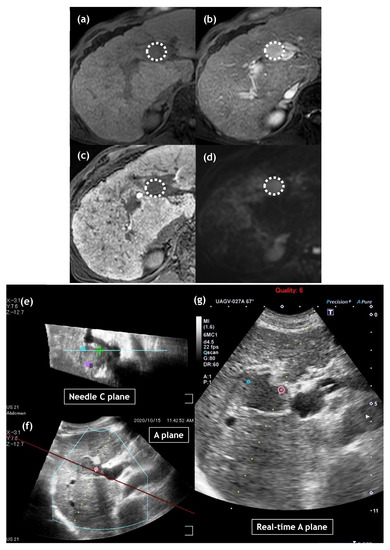

- Sugimoto, K.; Moriyasu, F.; Kobayashi, Y.; Saito, K.; Takeuchi, H.; Ogawa, S.; Ando, M.; Sano, T.; Mori, T.; Furuichi, Y.; et al. Irreversible electroporation for nonthermal tumor ablation in patients with hepatocellular carcinoma: Initial clinical experience in Japan. Jpn. J. Radiol. 2015, 33, 424–432. [Google Scholar] [CrossRef]

- Sugimoto, K.; Moriyasu, F.; Saito, K.; Kobayashi, Y.; Itoi, T. Multimodality imaging to assess immediate response following irreversible electroporation in patients with malignant hepatic tumors. J. Med. Ultrason. 2017, 44, 247–254. [Google Scholar]

- Sugimoto, K.; Abe, M.; Yoshimasu, Y.; Takeuchi, H.; Kasai, Y.; Itoi, T. Irreversible electroporation of hepatocellular carcinoma: The role of ultrasonography. Ultrasonography 2020, 39, 229–237. [Google Scholar] [CrossRef] [PubMed]